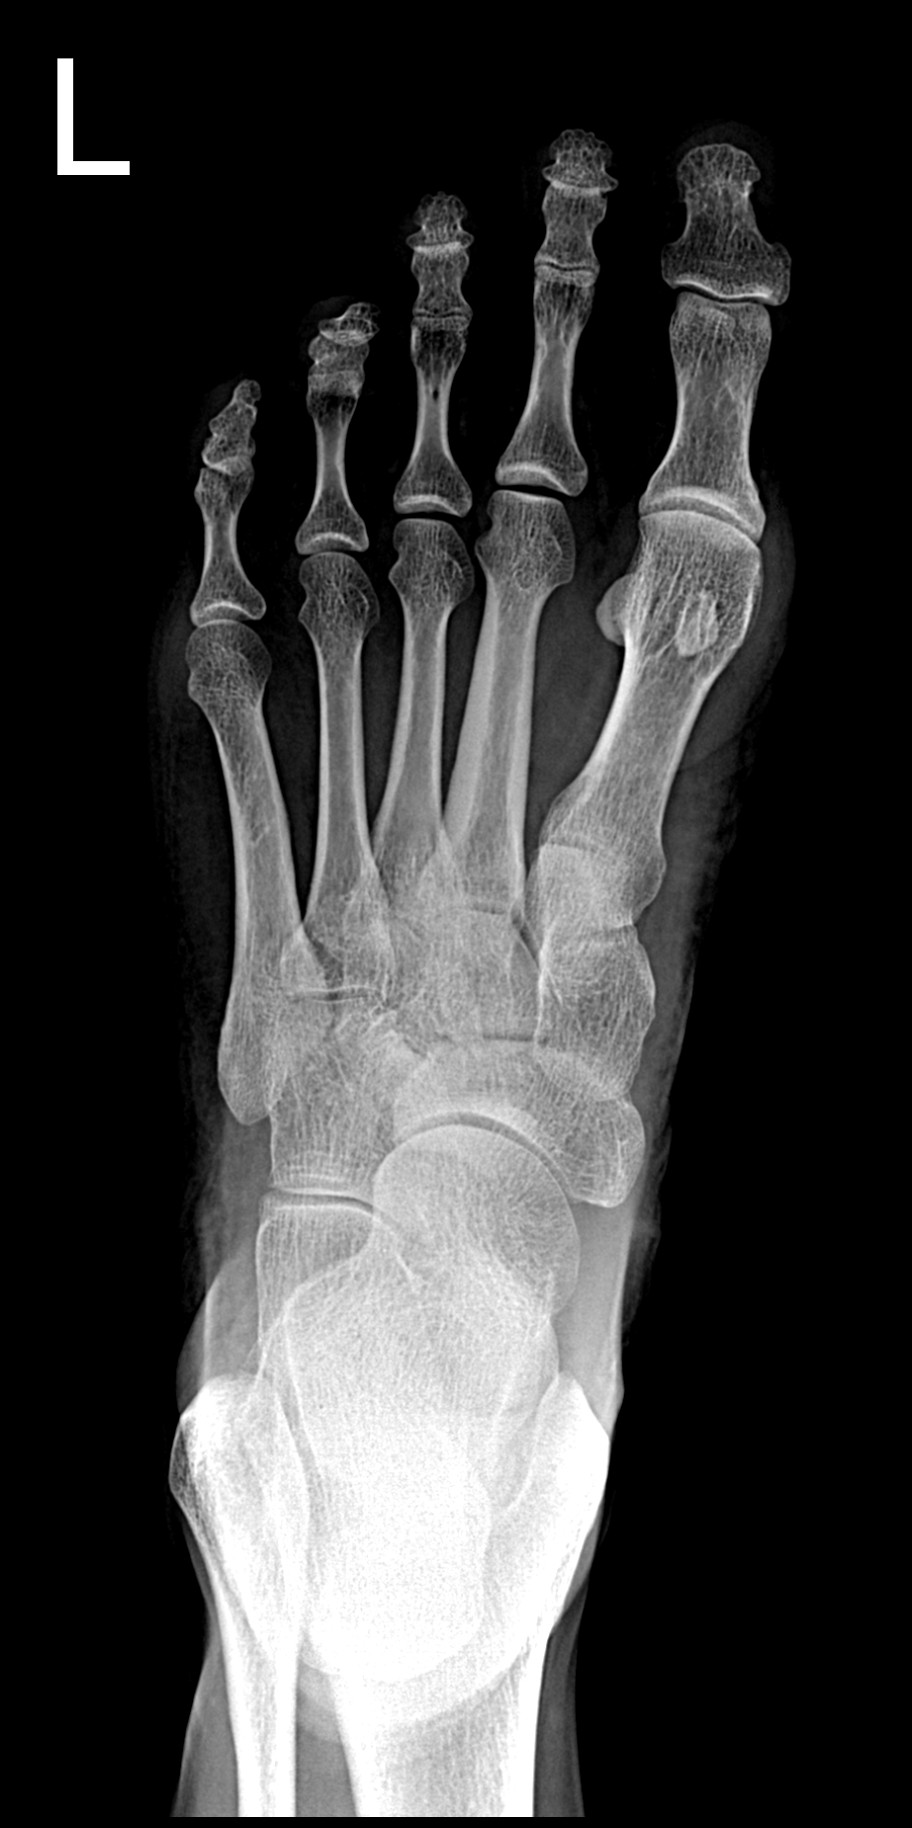

• Clinical Images